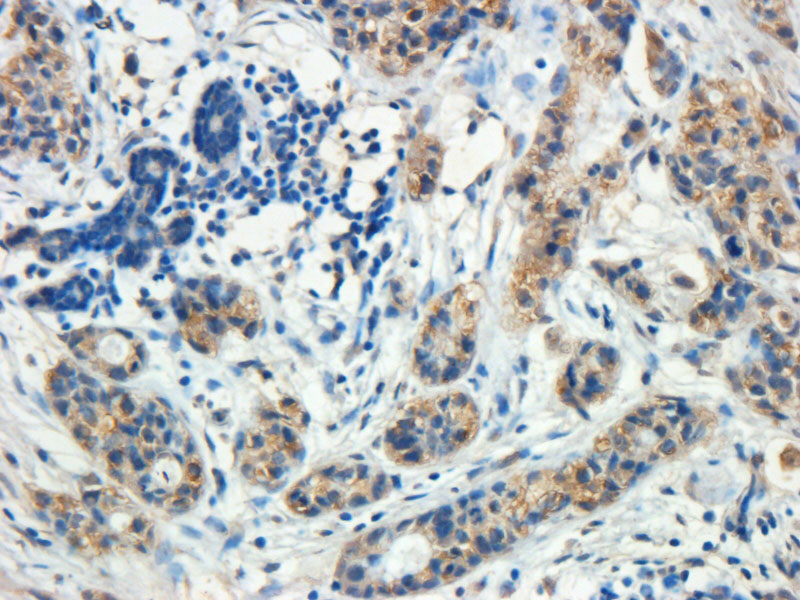

APR12171G (5 μg/ml) staining of paraffin embedded Human Breast cancer. Heated antigen retrieval with citrate buffer pH 6, DAB-staining. |